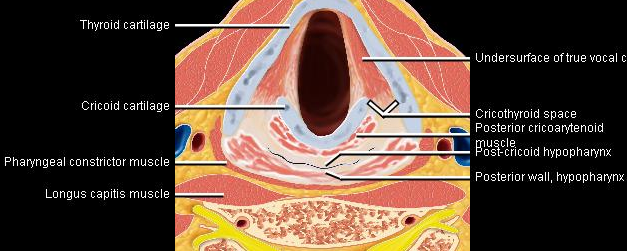

Phonation and dysphagia involve multiple coordinated structures in the larynx and pharynx. Radiation induced dysphagis appears to be related to dose to the phyaryngeal constrictor muscles and specific regions of the supraglottic and glottin larynyx.

Speech is impacted by doses to the epiglottis, base of tongue, aryepiglottic folds, false vocal cords upper esophageal sphincter and cricoid cartilage.